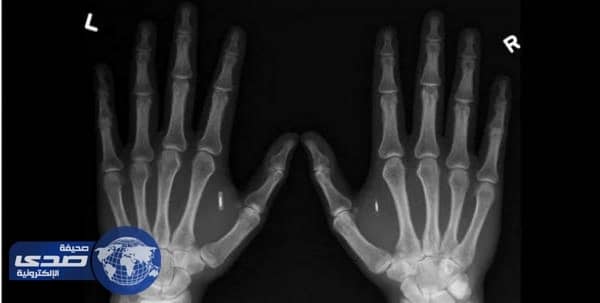

تقوم شركة سويدية ناشئة في مجال التكنولوجيا بزرع رقاقات داخل أيادي موظفيها منذ عام 2015 وحتى الآن، حتى بلغ عدد الموظفين المزروع بأجسادهم رقائق إلكترونية بحجم حبة الأرز، 150 من أصل 3000 موظف.

وأوضحت الشركة أن عملية الزرع تمر بسلاسة من دون ألم مثل أي " حقنة " في واحدة من الأيدي في الجهة اليمنى من إصبع الإبهام دون حدوث نزيف دم كما يعتقد البعض، وتتم العملية بشكل مجاني دون أن تُكلف الموظف أي رسوم.